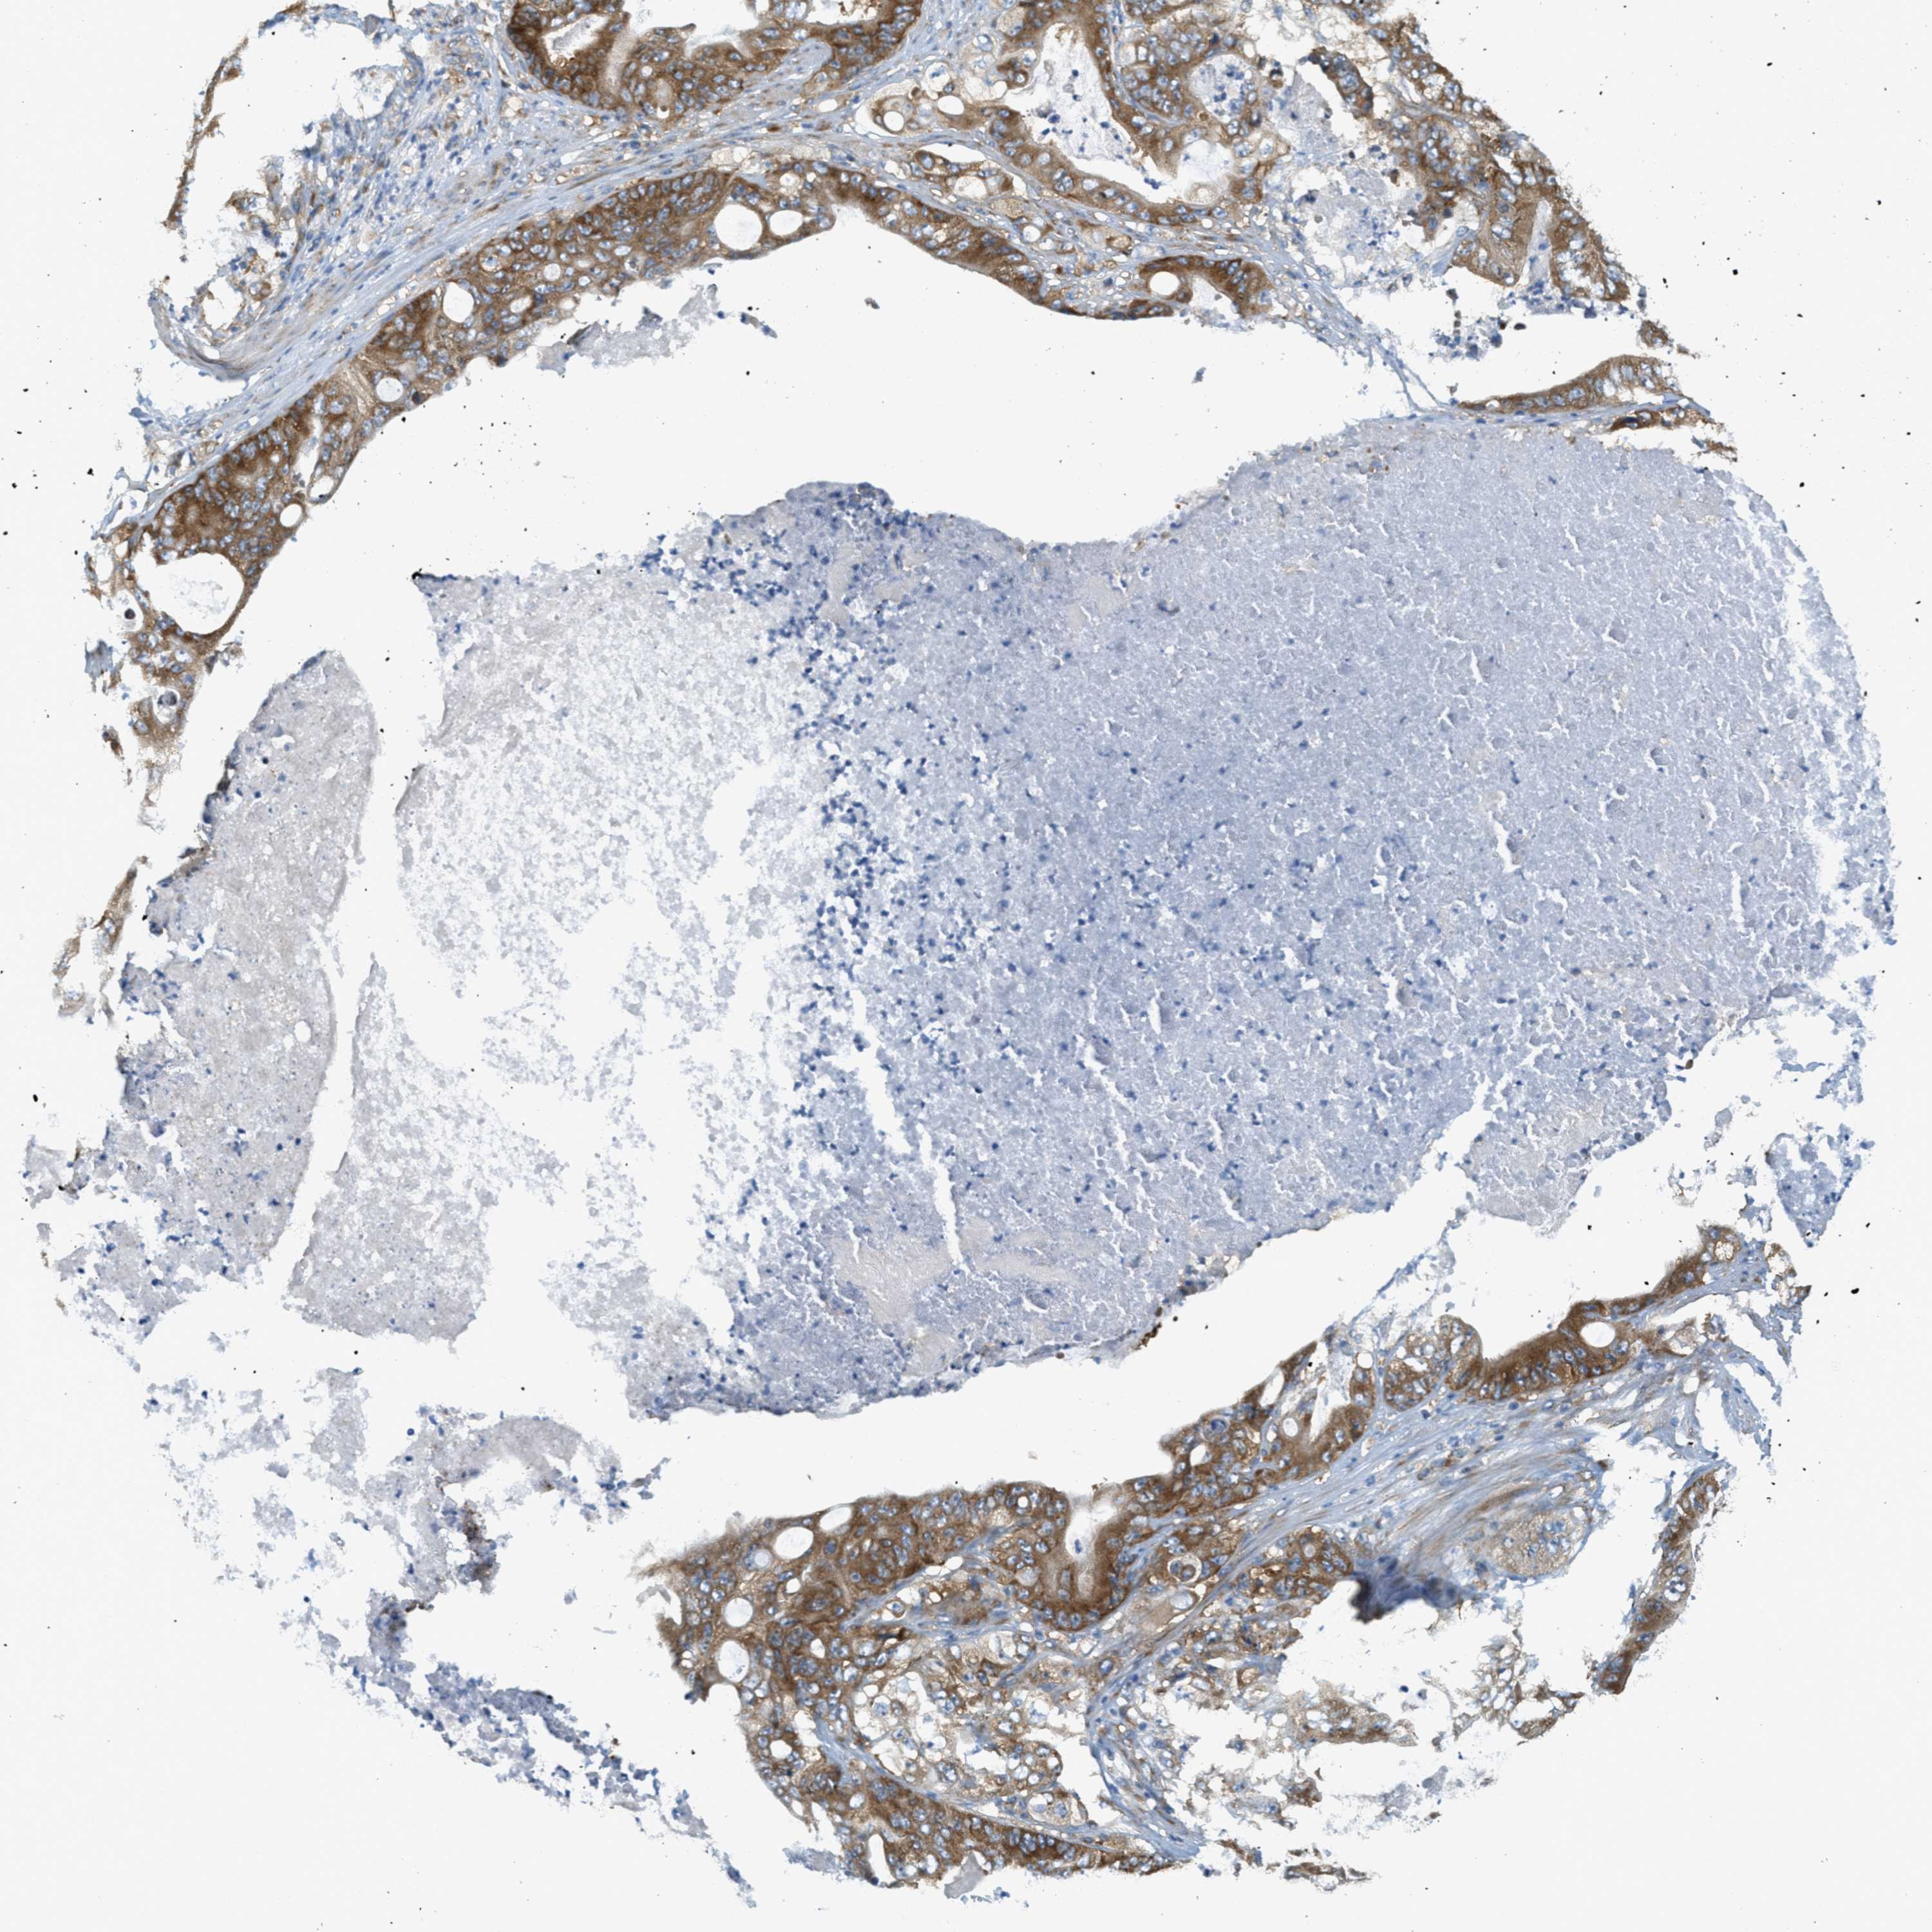

STOMACH CANCER - Protein expressioni

A mouse-over function shows sample information and annotation data. Click on an image to view it in a full screen mode. Samples can be filtered based on level of antibody staining by selecting one or several of the following categories: high, medium, low and not detected. The assay and annotation is described here.

Antibody stainingi

Antibody staining in the annotated cell types in the current human tissue is reported as not detected, low, medium, or high, based on conventional immunohistochemistry profiling in selected tissues. This score is based on the combination of the staining intensity and fraction of stained cells.

Each image is clickable and will lead to virtual microscopy that enables deeper exploration of all samples and also displays staining intensity scores, fraction scores and subcellular localization as well as patient and tissue information for each sample.

Antibody HPA017578

Staining

High

Medium

Low

Not detected

Intensity

Strong

Moderate

Weak

Negative

Quantity

>75%

75%-25%

<25%

None

Location

Nuclear

Cytoplasmic/membranous

Cytoplasmic/membranous,nuclear

Adenocarcinoma, NOS